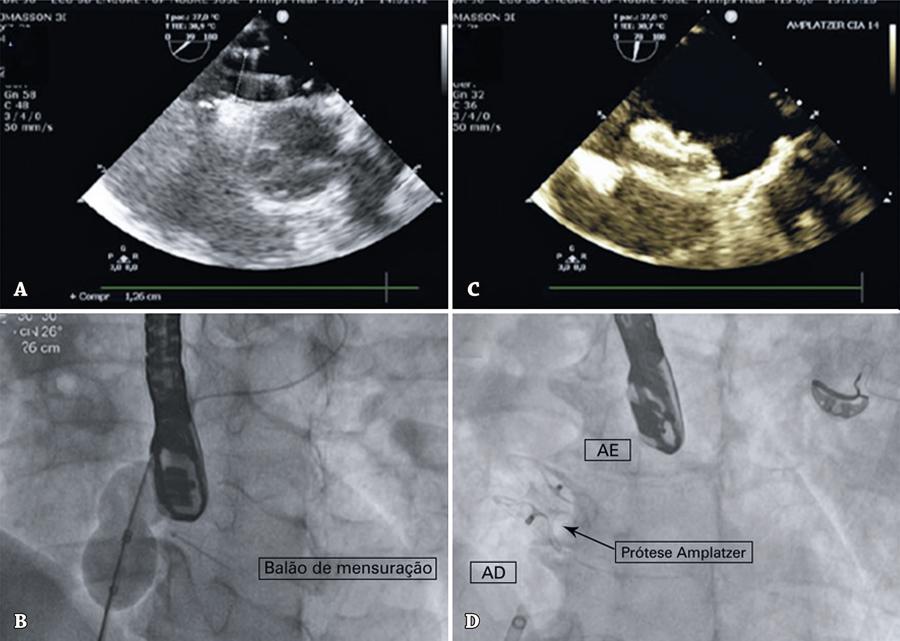

Figura 4

Etapas do procedimento. (A) Ecocardiografia do balão estirado no forame oval patente. (B) Imagem no cateterismo do balão estirado no forame oval patente. (C) Imagem ecocardiográfica da prótese de comunicação interatrial implantada vista em perfil. (D) Imagem no cateterismo da prótese de comunicação interatrial implantada.

AD: átrio direito; AE: átrio esquerdo.